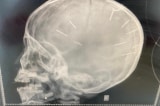

Luật sư bảo vệ quyền và lợi ích của bé Ngọc A. – ông Lê Hồng Hiển cho hay sau khi khám nghiệm tử thi, cơ quan chức năng xác định trong đầu của bé Ngọc A. có tất cả 10 chiếc đinh chứ không phải 9 chiếc như trước đó, báo Dân Việt dẫn lời. Những chiếc đinh này dài khoảng 2 cm, hiện đã được bàn giao cho công an để phục vụ quá trình điều tra. Thông tin trên được báo Dân Trí xác nhận với luật sư Hiển qua cuộc trao đổi vào sáng 13/3.

Bố cháu bé cho hay đinh được lấy ra khỏi hộp sọ bé A. là loại đinh làm mộc dài khoảng 1-2 phân, một đầu tròn và đuôi nhọn.